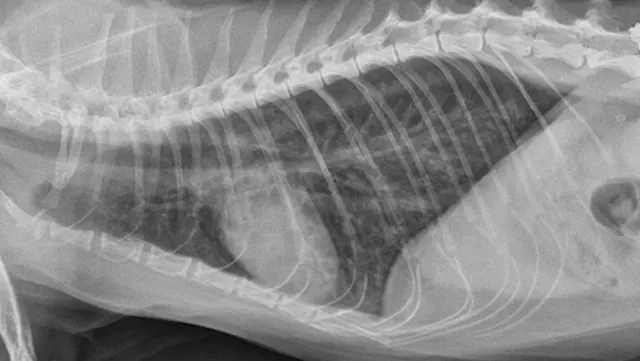

Primary cardiac disease that leads to CHF-related pulmonary edema commonly causes diffuse (perihilar in the dog) or variable (in the cat) interstitial and alveolar patterns. The vertebral heart score (VHS) is an objective method for evaluating the size of the cardiac silhouette (see Steps to Measure VHS). Certain cutoff values are used to determine whether acute respiratory distress is primarily pulmonary or cardiac in origin and to guide initial therapy for stabilization and planning for definitive cardiac or respiratory workup. A VHS <11.4 in the dog can help rule out mitral valve disease–related CHF as a cause for respiratory signs.3 Although an increased VHS can be associated with primary cardiac disease, it is not a specific characteristic in small-breed dogs because of their thoracic conformation.3 In the cat, a left lateral VHS ≤7.9 can reasonably rule out the presence of heart disease.4 Additional radiographic changes associated with primary cardiac disease include left atrial enlargement and pulmonary venous distension (Figures 1 and 2). Pleural effusion can be associated with CHF and primary pulmonary disease. A miliary pattern and/or solitary soft tissue densities in the lungs are indicative of primary pulmonary disease (Figure 3). Hyperinflation of the lung and distinct peribronchial markings are supportive of lower airway disease, although peribronchial markings can be found in the cat with CHF.

Right lateral thoracic radiograph of a dog that was presented with labored breathing and a moist cough. The patient had a history of a heart murmur, and the breathing pattern was synchronous with increased effort on inhalation. Thoracic auscultation revealed diffuse, soft moist crackles and a 4/6 left systolic heart murmur over the mitral region. Butorphanol and furosemide were administered and the patient was allowed to rest with supplemental oxygen before radiography. Radiographs showed a VHS of 12.5, significant left atrial enlargement (white arrows), and pulmonary venous distension (black arrows) consistent with left-sided heart failure. Mitral valve insufficiency caused by valvular endocardiosis was confirmed with echocardiography.